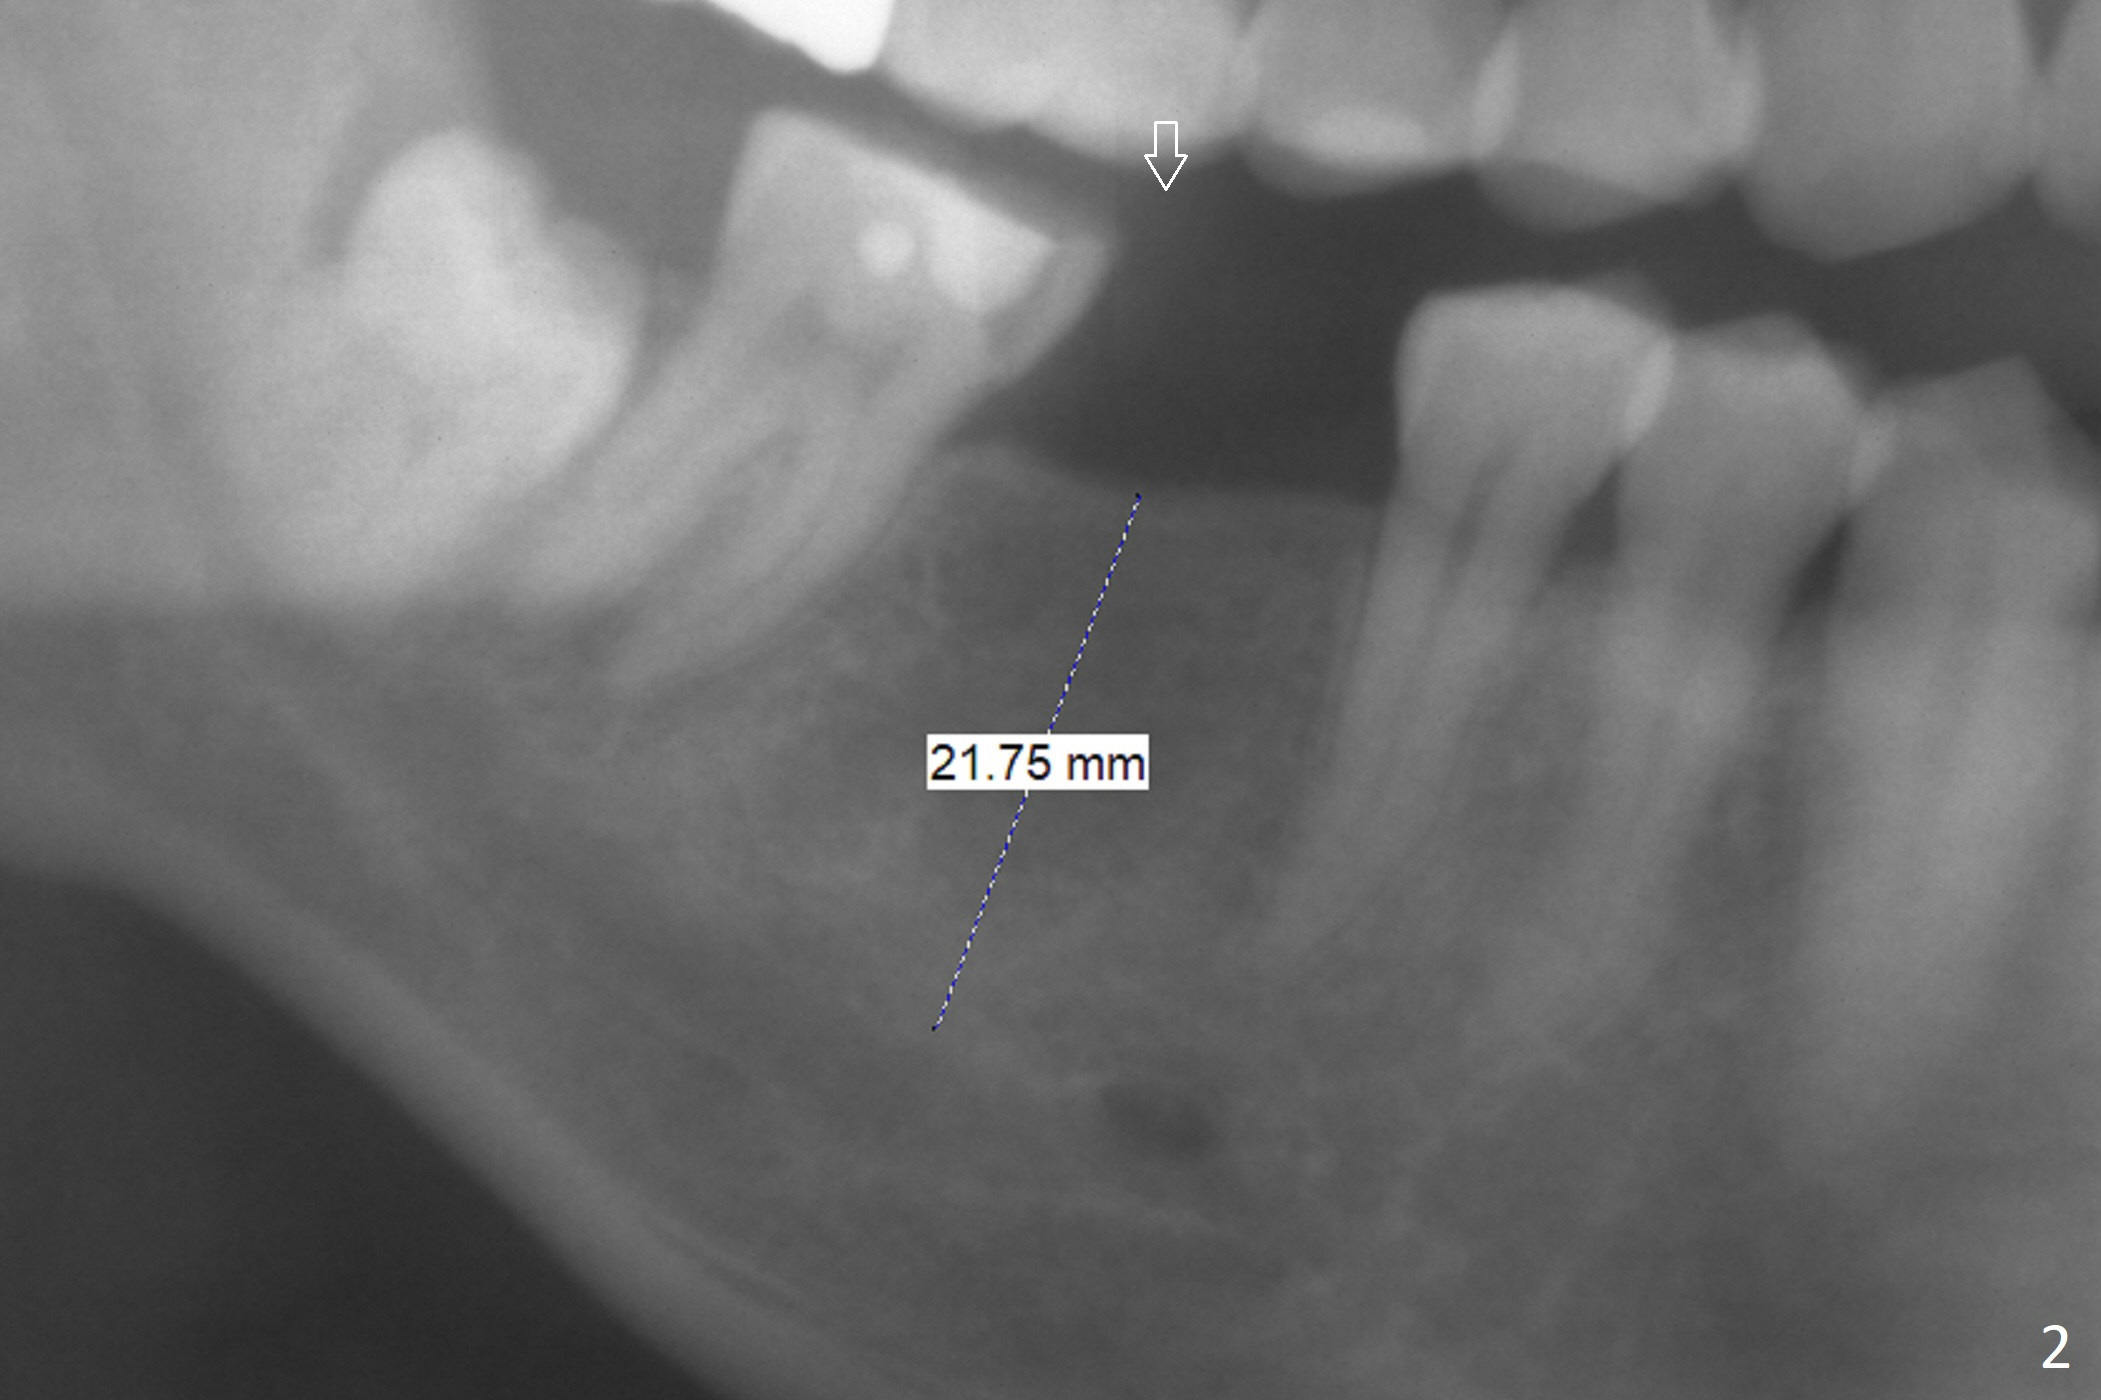

A 51-year-old man has a pyramidal ridge at #30 (Fig.1) with mild supraeruption of the opposing tooth (Fig.2 arrow). Ridge reduction will be done (Fig.3 red curved lines) prior to Bicon implant placement (green). A healing abutment is to be placed, followed by periodontal dressing.